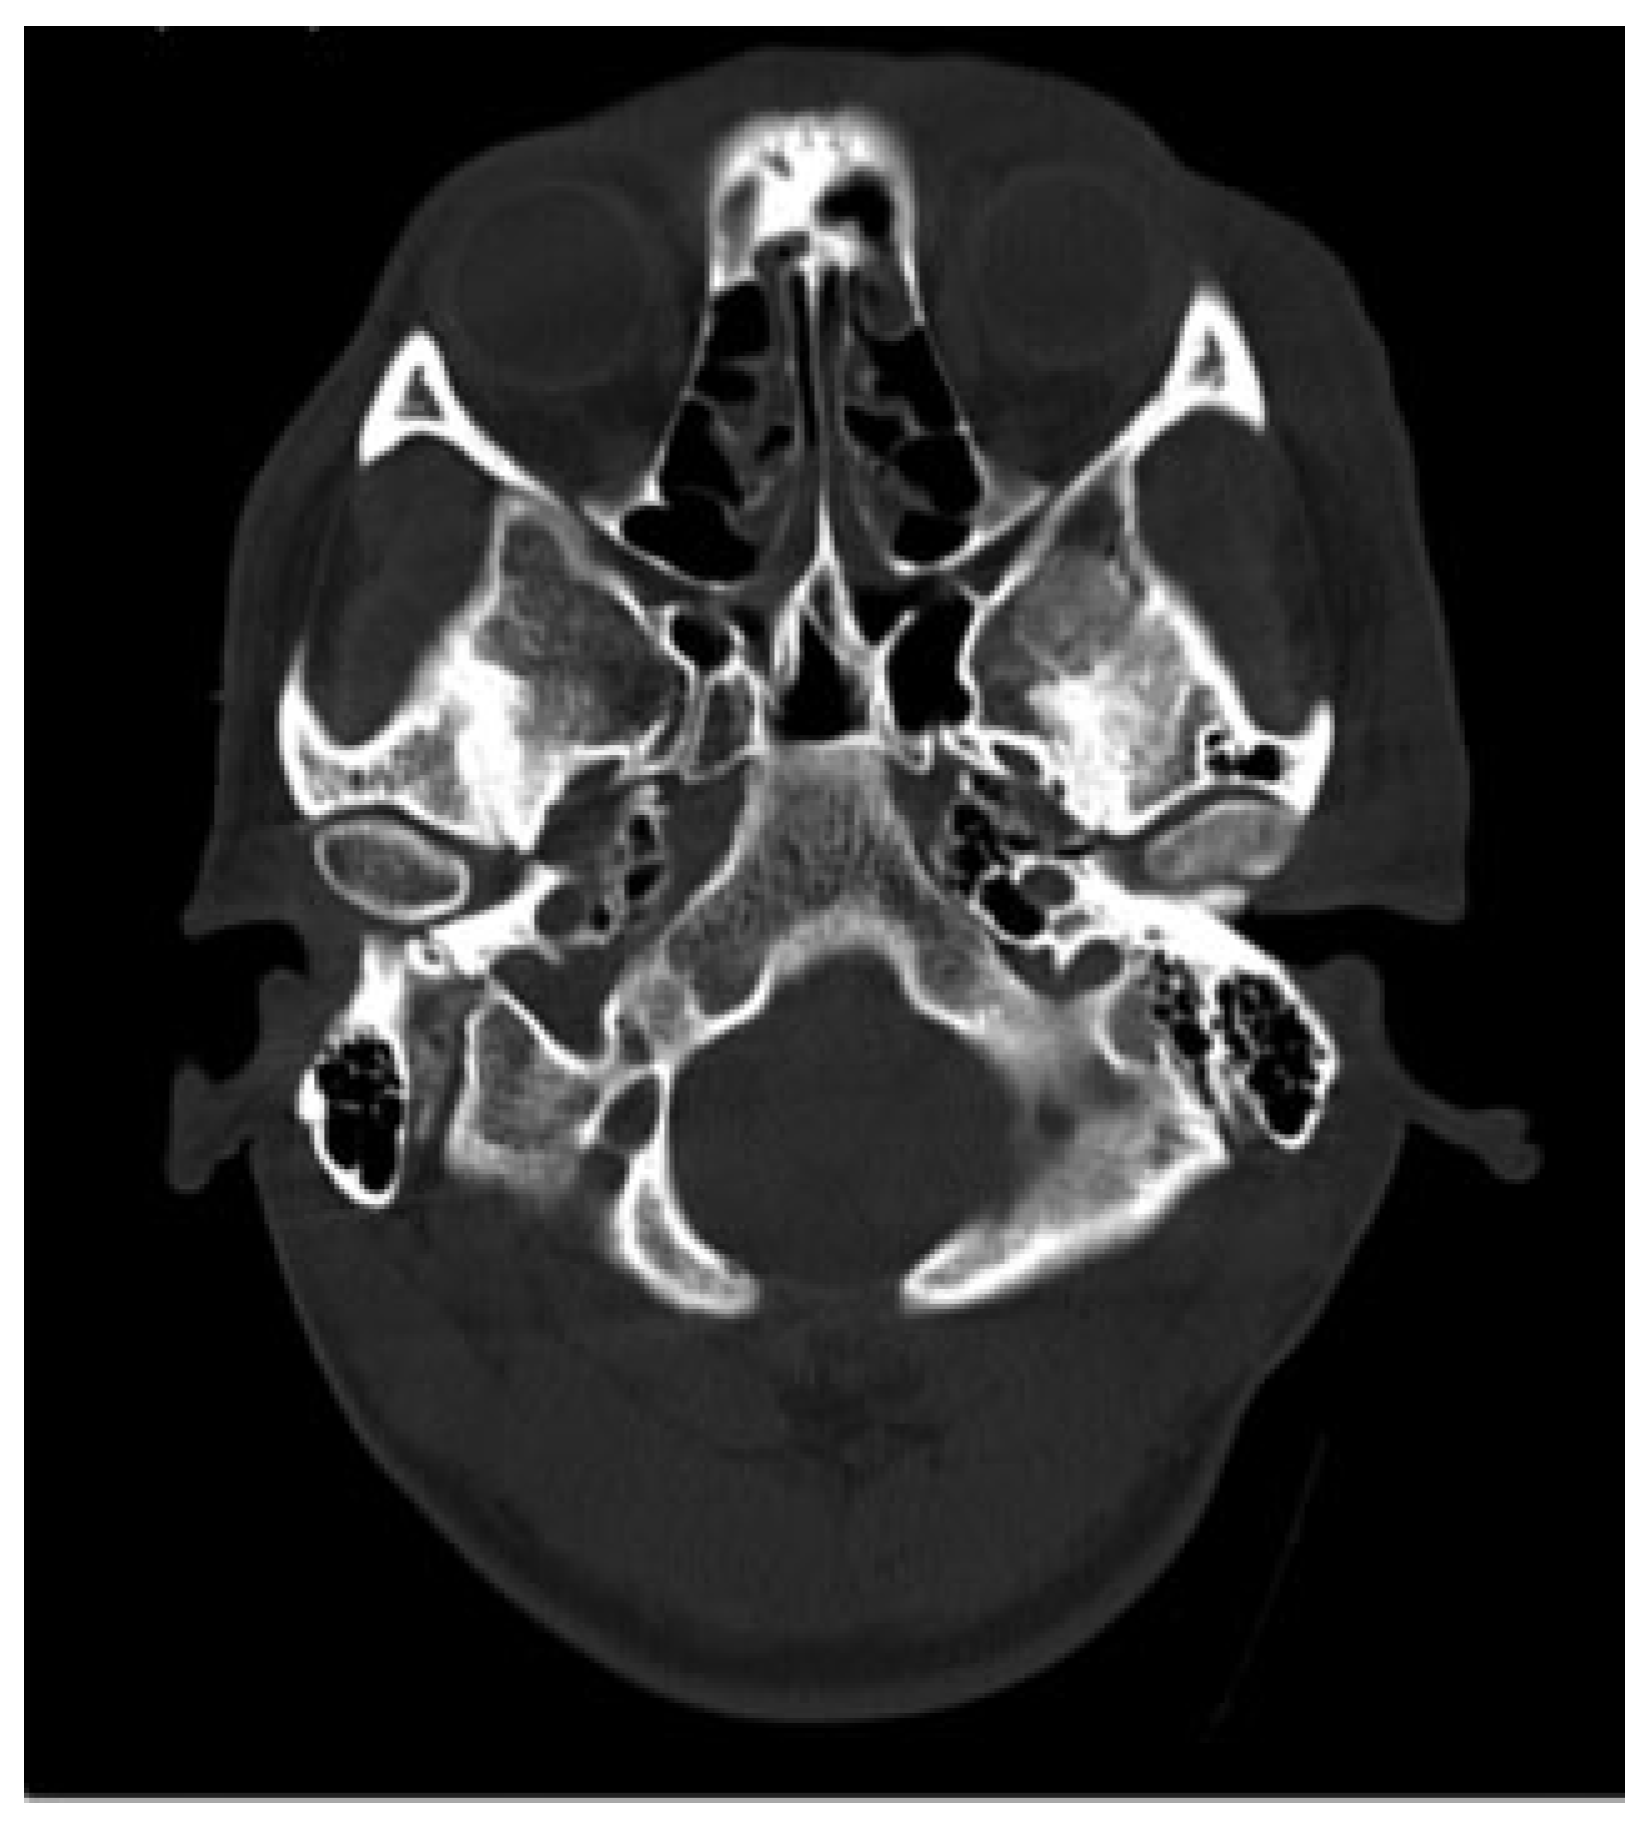

Examination revealed maximum mouth opening was 42 mm with 15 mm of anterior open bite upon closing. Computed tomographic (CT) scan that was taken immediately post-MVA shows no fractures to his facial skeleton and both condylar heads were located in the glenoid fossae ([Figure 1]). He was subsequently sent for another CT scan to view the position of the condyles. Both condylar heads of the mandible were anteriorly dislocated from the TMJ fossae and were located at bilateral infratemporal fossae ([Figure 2]). Closed reduction of the TMJ was attempted for a few times; however, it was unsuccessful because of the stiffness of muscle of mastication.

Figure 1. Computed tomographic scan immediately post–motor vehicle accident shows both condylar heads located in the glenoid fossa.